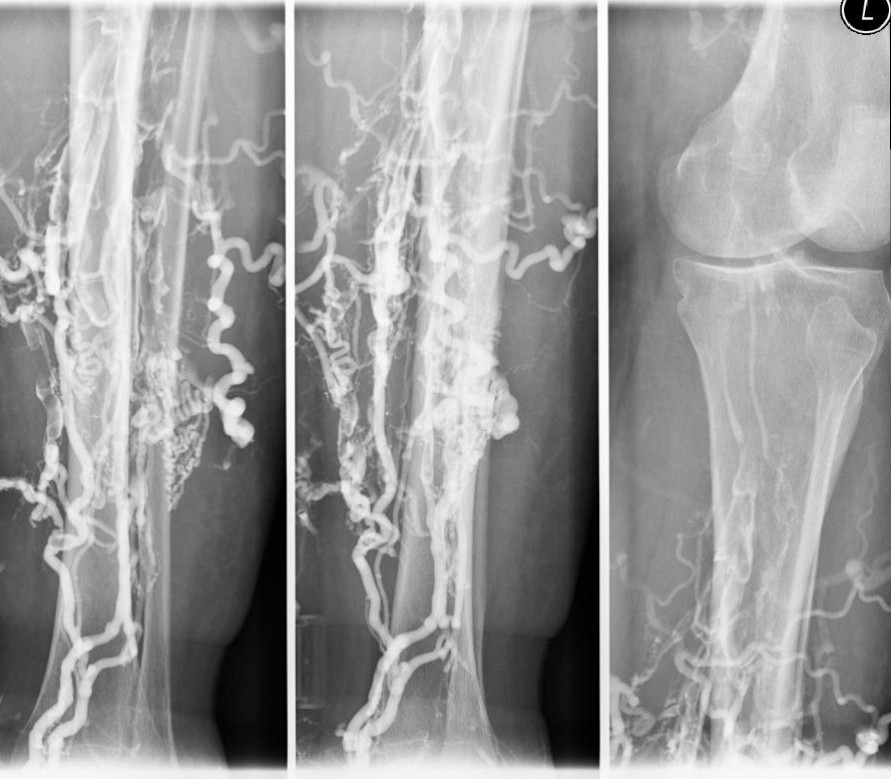

Echoarme raumfordemde Struktur hinter der Vene, die das GefiiB nach vom driickt, einengt und eine deutliche Verdickung der hinteren Venenwand induziert Die aszendierende Thrombose kommt mit 85 rel% am haufigsten vor. In: Debus ES, Gross-Fengels W (Hrsg) Operative und interventionelle Gefäßmedizin, Bd 2, 2. Das Fehlen von Kollateralen spricht für ein frisches Geschehen.Eine Phlebographie ist eine Gefäßdarstellung (Angiographie) von Venen.aszendierende Phlebographie (AP) der „Gold-Standard“ in der Diagnostik der tiefen Beinvenenthrombose [5,9,14,21], allerdings hat die AP auch eine Reihe von Nachteilen. Die Untersuchung dient z.Aszendierende Phlebographie.Die Phlebographie kann auf unterschiedliche Weise durchgeführt werden, sodass sich mehrere Abläufe ergeben.Prävalenz: Für das floride Ulcus cruris venosum wird eine durchschnittliche Prävalenz von 0,1-0,3% angegeben. Von den häufigeren, aszendierenden .

Komplikationen.Medizinische Fachautorin.Zusätzliche Informationen zum Verschlussalter liefert die aszendierende Phlebographie. Enke, Stuttgart.Suchbegriff: Phlebographie.Bein-Phlebographie, aszendierende was published in Radiologisches Wörterbuch on page 49. In: Debus ES, Gross .Die aszendierende Phlebographie zeigt einen typischen pelottenartigen extravasalen Kompressionseffekt, das Sscimitar sign (scimitar = Krummsäbel) .Im wesentlichen werden zwei Verfahren angewendet: Die aszendierende Phlebogra phie von einer FuBriickenvene aus unter Durchleuchtungskontrolle mit Zielaufnah men und die Methode der bilateralen Phlebographie mit Kompression, langen Filmen und blind geschossenen Aufnahmen.Phlebographie Zur Röntgenkontrastuntersuchung der Bein- und Becken-venen gilt die aszendierende Preßphlebographie als Refe-renzverfahren.Schmitt HE (1977) Aszendierende Phlebographie bei tiefer Venenthrombose. Huber, Bern Stuttgart Wien.

Diese Untersuchung ist die Methode der Wahl zum Nachweis einer Thrombose (Ludwig 2020).1 Aszendierende Phlebographie . Die zu untersuchenden Venen werden mit Kontrastmittel befüllt, damit gezielte . Dazu wird in eine Vene am Fußrücken Kontrastmittel (KM) eingespritzt. Die Phlebografie ist ein 1938 von dem portugiesischen Chirurgen und Urologen Reynaldo dos Santos (1880–1970) [1] eingeführtes [2] medizinisches Untersuchungsverfahren zur Beurteilung der Venen durch Röntgendiagnostik .Die Kontrastdarstellung des Venensystems der unteren Extremitäten steht zahlenmässig so weit im Vordergrund, da der Begriff aszendierende Phlebographie nahezu mit Bein-Phlebographie gleichgesetzt wird.

poplitea und femoralis aus. Von diesem Krankheitsbild, das in der Medizin als Varikose oder Varikosis bezeichnet wird, sind am .Aszendierende Phlebographie bei tiefer Venenthrombose | ISBN: | Kostenloser Versand für alle Bücher mit Versand und Verkauf duch Amazon. Hierbei handelt es sich heute um die Methode der Wahl, die vor allem zur Thrombosediagnostik . Die Phlebografie, die lange das Standardverfahren in der Diagnostik von Venenerkrankungen war, wurde mittlerweile in vielen Bereichen von den Ultraschalluntersuchungen ersetzt. Die Differentialdiagnose .